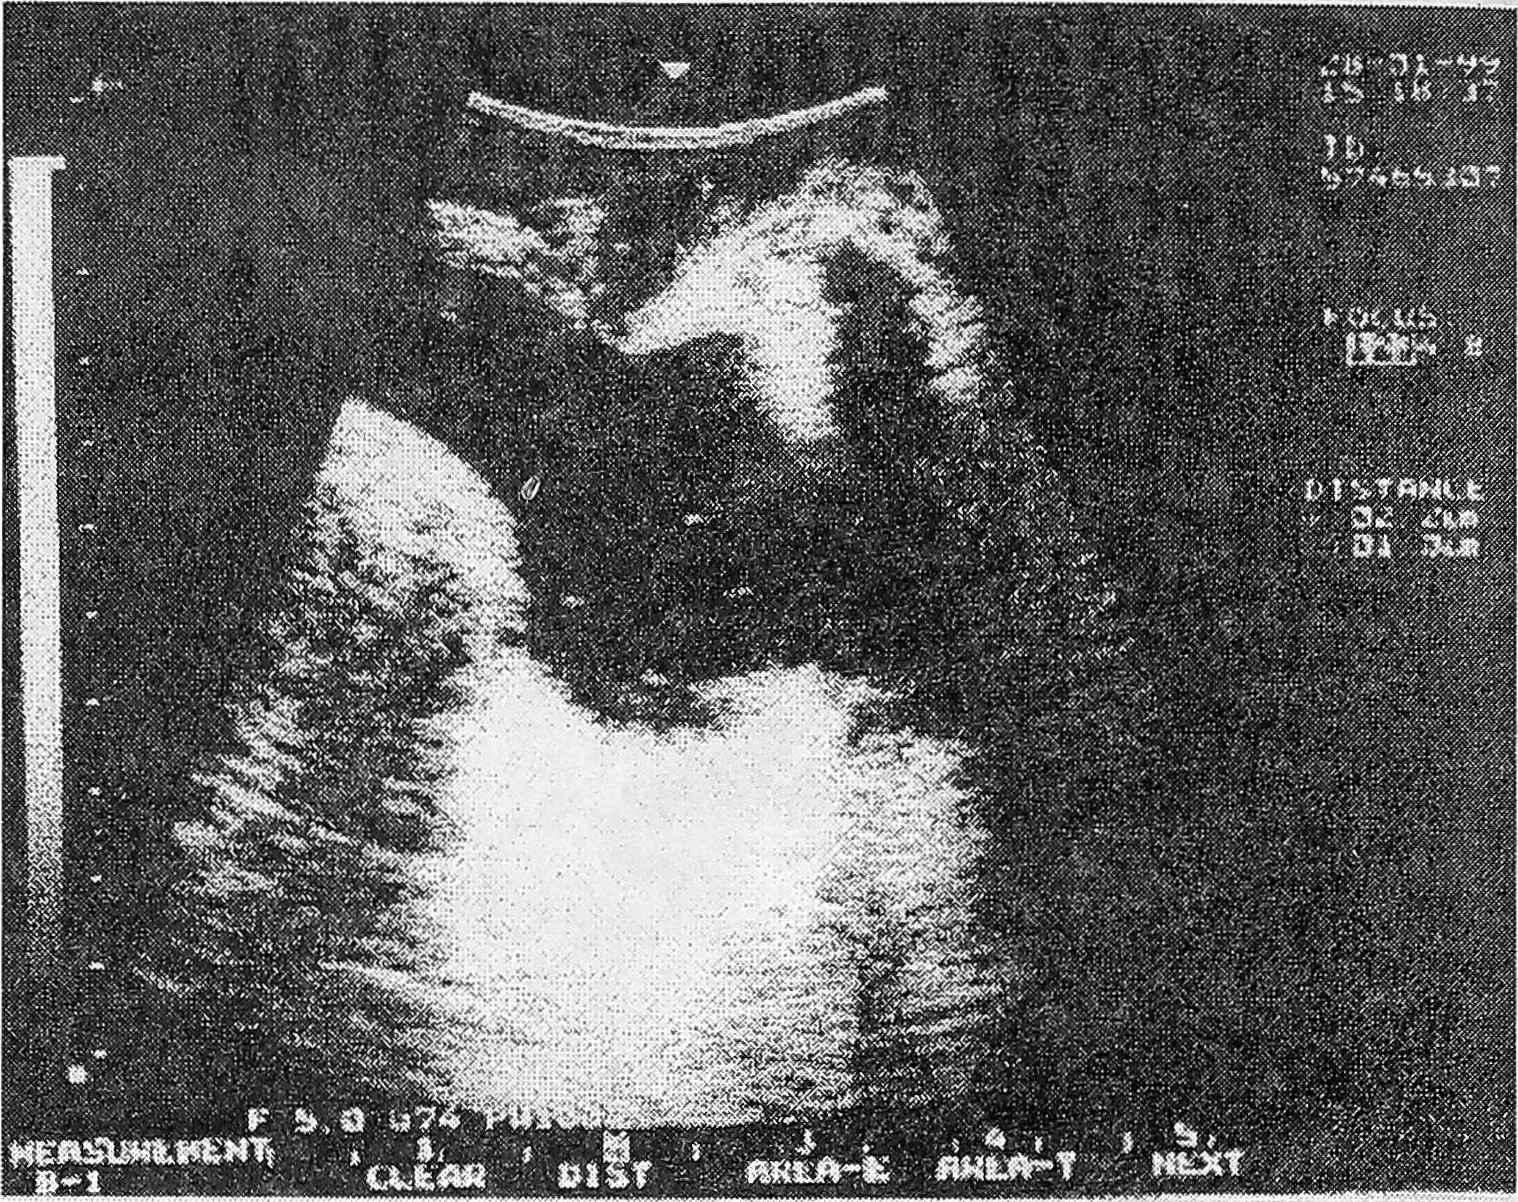

В результате ультразвукового сканирования у 25 женщин с уретритом получены следующие данные: позыв на мочеиспускание у всех женщин появился при ретроградном заполнении мочевого пузыря теплым раствором фурациллина в количестве от 50 до 150 мл (в среднем 98,8 мл), при этом длина уретры (при трансвагинальном сканировании) варьировала от 2,0 до 3,2 см (в среднем 2,57 см), ширина составляла от 0,3 до 1,0 см (в среднем 0,67 см). Форма уретры была разной: овальная у 16 (64,0% ±12,0) женщин, воронкообразная у 6 (24,0% ±17,4), колбообразная у трех (12,0%±18,7) (рис. 1, 2, 3). При стандартном заполнении мочевого пузыря (150-250 мл) образование цистоуретральной воронки наблюдалось у двух (8,0%±19,1) женщин, при этом отмечено укорочение уретры на 0,2-0,5 см (в среднем на 0,32 см), что находится в рамках физиологических колебаний. Проба Маршала во всех наблюдениях была отрицательной, т.е. недержания мочи при заполнении мочевого пузыря не было у всех пациенток. Остаточная моча в количестве 30,0 мл определялась лишь у одной пациентки, у которой помимо признаков уретрита имел место и острый цистит, эхографически видный как утолщение стенок мочевого пузыря и яркого свечения полости слизистой мочевого пузыря (рис. 4).

Рис. 1. УЗ-сканирование уретры (овальная форма).